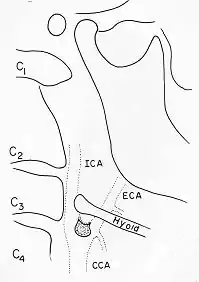

Panoramic radiographs have the capability to demonstrate a portion of the neck and display atheromas (calcifications in the carotid artery) which are an indication of both local and generalized (systemic) atherosclerosis. Atherosclerosis of the coronary arteries leading to myocardial infarction (heart attack), and atherosclerosis of the carotid artery leading to stroke are the number one and number three most common causes of death in the United States.[6]

There is interest to look at panoramic radiographs as a screening tool, however further data is needed with regards if it is able to make a meaningful difference in outcomes.[7]

Epidemiology: general public and high risk groups

Additional research projects have further determined the prevalence rate of these atheromas in the general population (3–5%)[8][9] and among high-risk groups (over 25% in: recent stroke victims,[10] individuals with obstructive sleep apnea syndrome,[11][12][13] postmenopausal women,[14] type 2 diabetics,[15][13][16] individuals with dilated cardiomyopathy,[17][13] and among individuals who have received radiotherapy directed at the neck,[18][19]). These findings have been corroborated by other several other researchers.[20][21][22][23][13]

Atherosclerosis is attributed to risk factors that include cigarette smoking, hyperlipidemia, obesity, diabetes mellitus, and hypertension (high blood pressure). These factors, however, do not fully account for the risk of disease. Atherosclerosis has been conceptualized as a chronic inflammatory response to endothelial cell injury[24] and dysfunction possibly arising from chronic dental infection. In 2010, using the previously validated Mattila panoramic radiographic index to quantify the totality of dental infection (i.e., periapical and furcal lesions, pericoronitis sites, carious tooth roots, teeth with pulpal caries, and vertical bony defects), Friedlander’s group determined that individuals with carotid artery atheromas on their panoramic radiographs had significantly greater amounts of dental infection/inflammation than atherogenic risk-matched controls devoid of radiographic atheromas.[25][26] While the Mattila index had been previously used to relate the extent of dental infection to coronary artery disease, this research is the first to link the full range of dental disease that it measures to panoramic radiographs evidencing calcified carotid artery atherosclerosis.